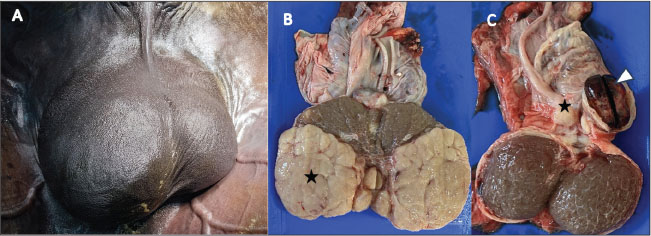

AbstractBackground: Testicular tumors are rare in horses, with seminoma being the most frequently described in the literature. In Morocco, many stallions used for Tbourida are intentionally kept intact, as uncastrated horses are traditionally viewed as symbols of prestige and cultural pride. This cultural practice increases the likelihood of detecting testicular pathology in mature stallions. Case Description: A 15-year-old Arabian–Barbe stallion used in Tbourida was presented for evaluation after the owner noticed a slow, progressive enlargement of the right testis over a period of more than 1 year. Clinical examination revealed a firm, enlarged right testicle, while the left testis appeared normal. Post-castration assessment revealed multiple firm, lobulated masses occupying roughly two-thirds of the right testis, and a small nodular lesion near the epididymal head on the left, associated with focal hemorrhage. Histopathology confirmed the coexistence of a seminoma and a leiomyoma within the same testis. Conclusion: This report describes the rare coexistence of seminoma and leiomyoma within the same equine testis, along with an epididymal hematoma. Together, these findings provide valuable insight into the spectrum of testicular lesions observed in stallions and highlight the importance of a comprehensive clinical assessment supported by histopathological examination for accurate diagnosis and appropriate management of testicular abnormalities in intact horses. Keywords: Seminoma, Leiomyoma, Testis tumor, Epididymal hematoma, Arabian–Barbe stallion. IntroductionTesticular tumors in horses are rare, and their true prevalence remains poorly defined in the literature (Leidinger et al., 2018). These neoplasms are classified as germ cell tumors (e.g., seminoma and teratoma), sex cord-stromal tumors (e.g., Leydig and Sertoli cell tumors), or tumors of other origins, such as lymphoma or smooth muscle neoplasms (Cooper and Valentine, 2002; MacLachlan and Kennedy, 2002; Valentine, 2009). Among germ cell tumors, seminoma is the most commonly reported in equids (Valentine, 2009; Govaere et al., 2010). Knowledge regarding equine seminomas remains limited and is largely derived from individual case reports, partly because most horses are castrated at a young age, restricting long-term observation of intact stallions (Schumacher, 1999; Valentine, 2009; Peeters et al., 2024). Interestingly, the number of published case reports relative to the small population of intact adult stallions suggests that testicular tumors may be more frequent than traditionally assumed (Brinsko, 1998; Valentine, 2009). Equine seminoma is typically observed in adult and older stallions, with the majority of published cases involving horses older than 10 years of age; reports in younger animals remain uncommon (Trigo et al., 1984; Brinsko, 1998; Weiermayer and Richter, 2009; Batista et al., 2024; Peeters et al., 2024). These tumors may develop in both descended and cryptorchid testes, with cryptorchidism considered a potential predisposing factor (Weiermayer and Richter, 2009; De Lange et al., 2015; Varner et al., 2015; Pasolini et al., 2016; Turner, 2019). Although equine seminomas are frequently classified as benign, malignant behavior and metastatic spread have been reported in horses, suggesting a more aggressive biological profile compared with other domestic species (Valentine, 2009; Agnew and MacLachlan, 2016; Meuten, 2020; Peeters et al., 2024). Although uncommon, testicular tumors can present significant clinical and management challenges, especially in regions where stallions are traditionally left intact. In Morocco, stallions are kept uncastrated to participate in traditional equestrian performance known as Tbourida, a practice deeply rooted in historical and cultural heritage (Talley and G, 2017). Tbourida was officially recognized as a national heritage sport during the reign of King Hassan II (1961–1999) and is performed during moussems (saints’ day celebrations), weddings, and national festivals. During these spectacular displays, teams of horsemen (sorba) ride in synchronized formations and fire gunpowder rifles in unison, showcasing discipline, coordination, and strength (Talley, 2017). In 2021, Tbourida was inscribed on UNESCO (2021) Representative List of the Intangible Cultural Heritage of Humanity, further highlighting its cultural significance. Owning an intact stallion carries social prestige and reflects tradition; therefore, castration is totally avoided. This management preference increases the likelihood of observing chronic testicular pathology in this special population. This report describes an unusual case of coexisting seminoma and leiomyoma in the testis of an Arabian–Barbe stallion used for Tbourida. Due to the limited information available on how these lesions present clinically, ultrasonographically, and histopathologically in horses, this case provides practical insight for veterinarians. Case DetailsA 15-year-old Arabian–Barbe stallion used for Tbourida was referred to the Equine Clinic of the Hassan II Agronomic and Veterinary Institute (Rabat, Morocco) after the owner noticed a gradual enlargement of the right testicle. The swelling had been apparent for more than 1 year but had become more obvious in recent months. This change began to affect the horse’s appearance during Tbourida performances, posing practical concerns, and the stallion had recently started to show mild signs of discomfort. During the physical examination, the stallion was calm, alert, and all vital parameters were within normal limits. The right testicle was markedly enlarged and firm on palpation, while the left testicle appeared normal in size and consistency (Fig. 1A). No scrotal edema was observed, and the horse showed no signs of pain during manipulation. Ultrasonographic evaluation of the right testis revealed heterogeneous tissue with multiple poorly defined hypoechoic regions, mainly in its caudal portion. On the left side, a small hypoechoic area was identified near an echogenic structure at the epididymal head, suggestive of a localized hematoma. Considering the chronicity of the lesion history and the imaging characteristics, testicular neoplasia was considered the most likely diagnosis.

Fig. 1. Marked scrotal asymmetry in an adult stallion, characterized by a pronounced enlargement of the right testicle (A). Post-castration gross examination shows multiple lobulated masses of variable size and beige to dark beige color occupying most of the right testicular parenchyma (B) (asterisks), with whitish fibrous areas visible at the center of the section (white arrows). A well-demarcated hemorrhagic lesion is observed cranially to the left testis at the level of the epididymal head (C) (arrowhead), consistent with a localized hematoma, with an adjacent nodular lesion (asterisk). Anesthesia and surgical procedureThe stallion was premedicated with acepromazine (Calmivet®, Vetoquinol; 0.02 mg/kg body weight, IV). After approximately 20 minutes, sedation was induced using xylazine (Rompun®, Bayer; 0.8 mg/kg body weight, IV). General anesthesia was induced with ketamine hydrochloride (Ketamine®; 2.2 mg/kg body weight, IV) combined with diazepam (Diaphram®; 0.05mg/kg body weight, IV) and subsequently maintained with isoflurane (Aerrane®, Baxter) delivered via inhalation, as previously described by Muir et al. (2018). Preoperative analgesia was provided using flunixin meglumine (Norbrook®, Norbrook Laboratories; 1.1 mg/kg body weight, IV). Prophylactic antibiotic therapy consisted of benzylpenicillin sodium (Norbrook®, Norbrook Laboratories; 22.000 IU/kg body weight, IM). Castration was performed using a standard inguinal approach under routine aseptic conditions as previously described by Sedrish and Leonard (2001). The spermatic cord and cremaster muscle were isolated by blunt dissection, the testis was exteriorized, and the ligament of the tail of the epididymis was transected. An emasculator was applied to the spermatic cord for approximately 5 minutes prior to transection, followed by placement of a security ligature. The surgical site was closed routinely in two layers. Histopathological examinationRepresentative tissue samples from the testicular masses were fixed in 10% neutral buffered formalin for 48 hours to 5 days. Tissue specimens were processed routinely by dehydration through a graded series of ethanol solutions (70%–100%), cleared, and embedded in paraffin. Paraffin-embedded tissues were sectioned at a thickness of 3–5 µm, deparaffinized, and stained with hematoxylin and eosin (H&E) according to standard histological techniques as described by Bancroft and Gamble (2008). Histological sections were examined using a light microscope to evaluate the morphological characteristics of the testicular tissue and associated lesions. Post-castration examinationPost-castration examination of the right testis showed multiple firm, lobulated masses of varying sizes, occupying approximately the caudal two-thirds of the parenchyma (Fig. 1B). The combined diameter of the masses was approximately 14 cm. The remaining parenchyma contained scattered pale, irregular areas interspersed with zones that appeared relatively preserved (Fig. 1B). On the left side, a small, well-circumscribed 3-cm nodule was found above the left testis, along with a localized hematoma at the epididymal head. The cut surface of the neoplastic tissue was beige to dark beige in color and firm in texture, while the hemorrhagic area appeared dark red-brown, with partly clotted blood and mild compression of the adjacent parenchyma (Fig. 1C). These observations confirmed bilateral involvement, with lobulated neoplastic tissue in the right testis and a peri-epididymal nodule with focal hemorrhage on the left (Fig. 1B and C). Histopathological findingsExamination of the testicular parenchyma revealed a neoplastic proliferation with a diffuse architecture and trabecular architecture (Fig. 2A, B). The neoplastic cells exhibited enlarged, anisokaryotic, hyperchromatic, and nucleolated nuclei, with clear cytoplasm (Fig. 2C, asterisk). The stroma contained fibrous septa, infiltrated by lymphocytes occasionally forming lymphoid aggregates (Fig. 2B, white arrow). No vascular emboli were observed, and the epididymis, tunica albuginea, rete testis, and spermatic cord were free of neoplastic invasion. These morphological features were consistent with a seminoma.